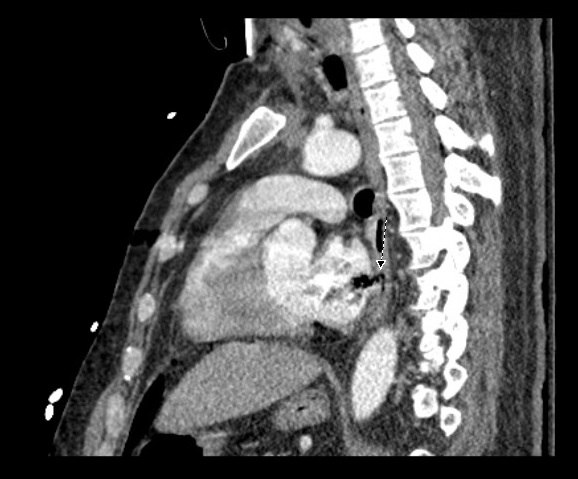

Case Presentation: We present a case of a 42-year-old male with a past medical history of atrial fibrilation (AF) on anti-coagulation (AC) who underwent left atrial radio-frequency ablation (RFA) and pulmonary vein isolation (PVI) and presented with confusion and bilateral upper and lower extremity weakness.The patient tolerated the procedure but complained of difficulty swallowing afterwards. Five days later, he began having malaise and GI upset which was associated with an episode of loose bright red blood bowel movement. He later became more confused, began to have weakness in all of his extremities, and was admitted to the hospital for workup. Imaging of the brain revealed multiple focal areas of subacute infarcts consistent with multiple embolic events involving the bilateral frontal lobes, left parietal and right temporal lobes. CT of the chest also revealed air next to the posterior wall of left atrium which was thought to be secondary to AEF as a complication of his RFA. His hospital course was complicated by seizure, sepsis secondary to aspiration pneumonia, and cardiac arrest requiring several rounds of chest compression. Immediately after he regained pulse, he was noted to be posturing with worse mental status, and a CT of the head showed multiple air emboli bilaterally with a higher stroke burden when compared to his initial CT scan. The patient was deemed non-operable, and was eventually discharged to long term acute care facility.